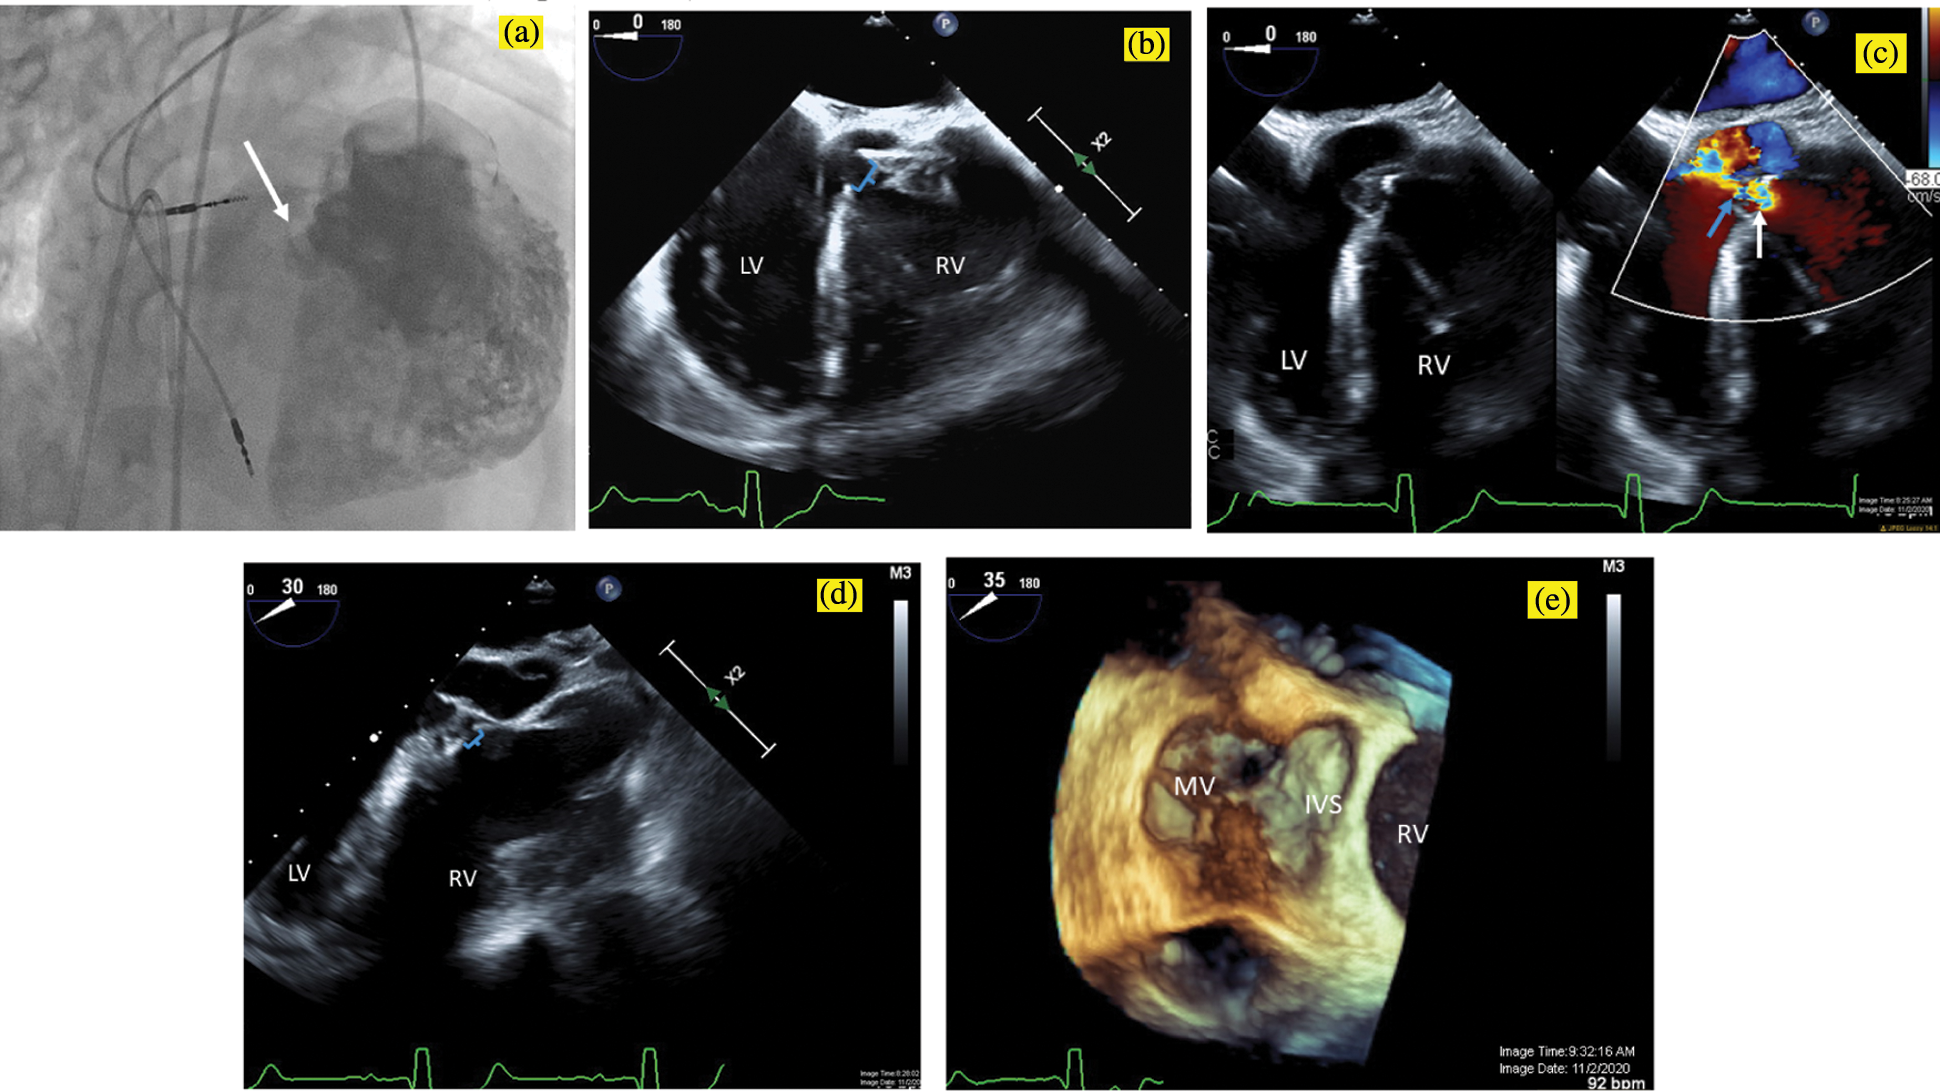

The patient was brought to the catheterization laboratory, where he underwent a hemodynamic evaluation and TEE. TEE demonstrated a single pmVSD partially covered by accessory tricuspid valve tissue billowing into the sub-pulmonary left ventricle (LV), with a single orifice in the aneurysmal tricuspid valve tissue that was 5 mm in diameter (Fig. 1). As expected, the VSD was remote from the aortic valve. The hemodynamic evaluation demonstrated a small magnitude left-to-right shunt (ratio of pulmonary to systemic blood flow of 1.4:1), normal pulmonary artery pressures and mildly elevated left-sided filling pressures (sub-aortic right ventricular end-diastolic pressure was 15 mmHg). Angiography was consistent with the TEE measurement (Fig. 1a).

Figure 1: Pre-intervention imaging. A power injection angiogram in an RAO/Cranial projection (a) demonstrates a single perimembranous VSD (white arrow), which is remote from the aortic valve and is partially covered by accessory tricuspid valve tissue, with a single orifice in the aneurysmal tricuspid valve tissue measuring 5 mm in diameter. Transesophageal echocardiogram in a zero-degree view similarly (b) demonstrates the 5 mm ventricular septal defect (brackets) with accessory tricuspid valve tissue partially covering the defect. With color compare (c), the VSD is seen in 2D on the left, and with the color flow on the right, aliasing can be seen beginning at anatomic VSD (white arrow) and continuing through the restrictive aneurysmal tricuspid valve tissue (blue arrow). Transesophageal echocardiogram in a 30-degree view (d) demonstrates the proximity of the VSD (brackets) to the aortic valve and in a 35-degree view with 3D Zoom acquisition (e) shows the VSD from the LV apex view with the anterior leaflet of the mitral valve on the left (MV). IVS, interventricular septum; LV, left ventricle; RV, right ventricle; VSD, ventricular septal defect